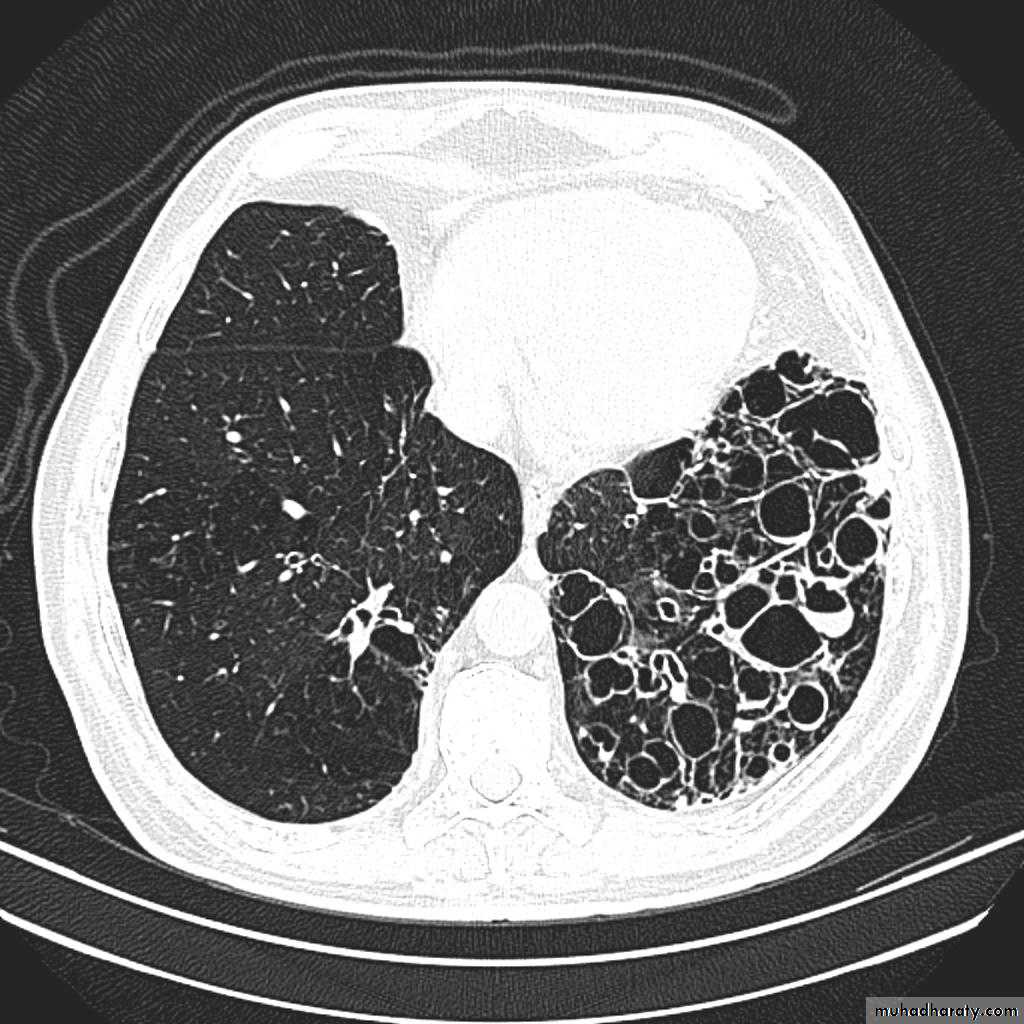

Pulmonary emphysema

Pulmonary emphysema is defined as the "abnormal permanent enlargement of the airspaces distal to the terminal bronchioles accompanied by destruction of the alveolar wall and without obvious fibrosis". Emphysema is one of the entities grouped together as chronic obstructive pulmonary diseaseRadiographic features

Plain film

Except in the case of very advanced disease with bulla formation, chest radiography does not image emphysema directly, but rather infers the diagnosis due to associated features :

hyperinflation:

1.flattened hemidiaphragm(s): most reliable sign

2.ncreased and usually irregular radiolucency of the lungs

3.increased retrosternal airspace

4.increased antero-posterior diameter of chest

5.widely spaced ribs

6.sternal bowing

7.tenting of the diaphragm

8.saber-sheath trachea

9.vascular changes paucity of blood vessels ( absent pulmonary markings in outer 1/3 of the lung fields )

10 .pulmonary arterial hypertension

pruning of peripheral vessels

increased calibre of central arteries

right ventricular enlargement

Pulmonary bullae are focal regions of emphysema with no discenible wall which measure more than 1cm in diameter